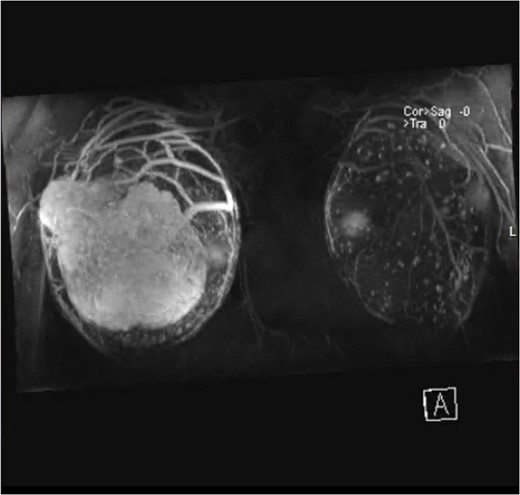

Magnetic resonance imaging (MRI) revealed anteriorly two large masses of the right breast, showing heterogeneous intensity and mass effect over the implant. Following contrast injection, peripheral heterogenous enhancement of the well-circumscribed oval mass of the right breast anteriorly occupying the superior lateral aspect measuring 10 cm × 6 cm2. Central necrosis is noted. Another smaller mass is seen on the lateral part, which is very close to the skin but with no invasion, measuring 4 cm × 2.6 cm (Fig. 2).